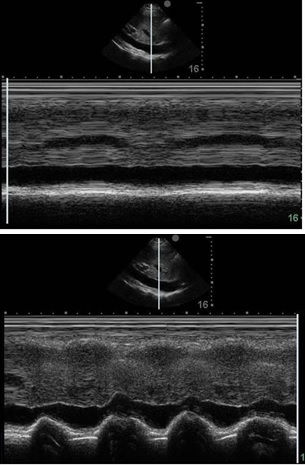

Heart Spontaneous Breathing Image